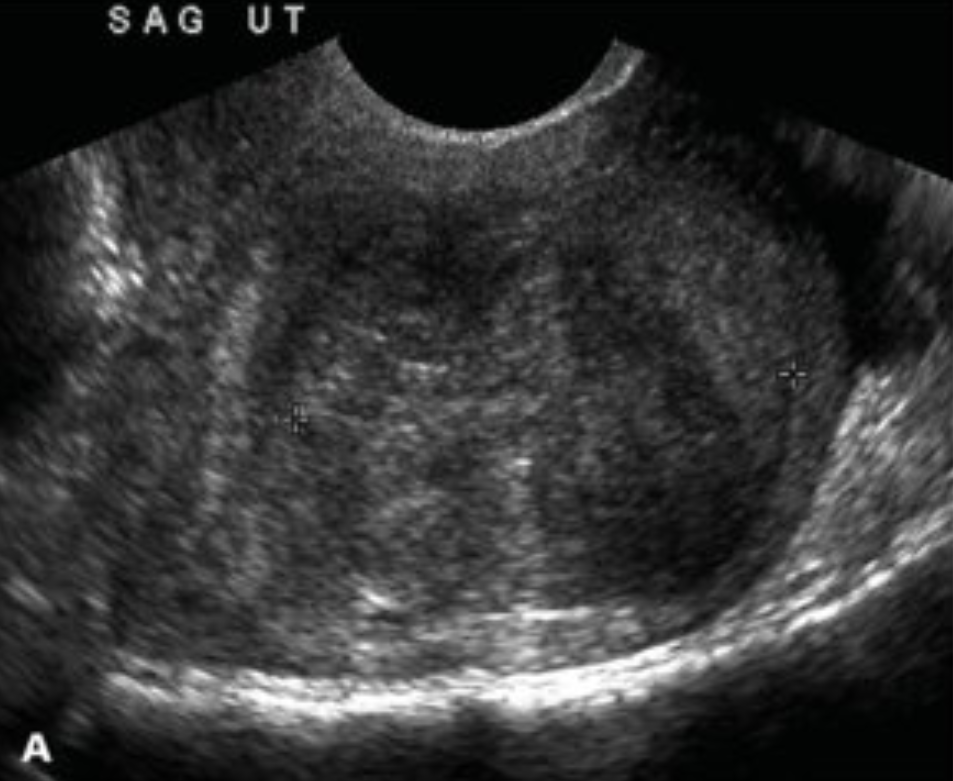

Ultrasound

• US in 2 weeks to assess the uterine size